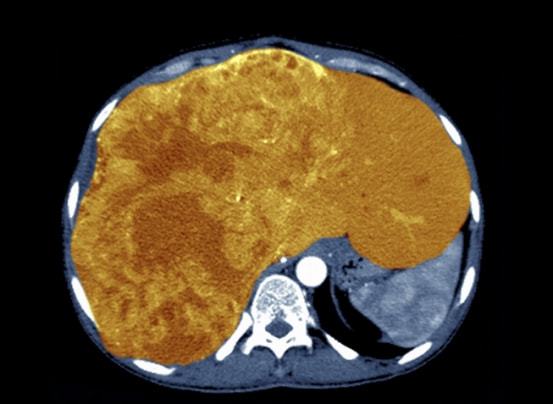

4:电子计算机X线体层摄影(CT) 可显示直径2cm以上的肿瘤。